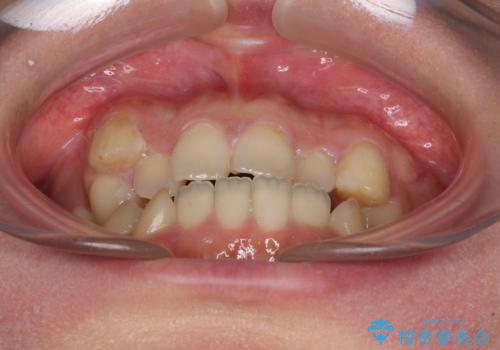

八重歯を抜歯矯正でスッキリと メタルブラケットでの矯正治療

- 八重歯と上下前歯のでこぼこを気にして来院された患者様です。

上下前歯部叢生のスペース獲得のため、上下顎左右小臼歯各1歯(計4本)と全ての親知らずを抜歯して、矯正治療を行うこととしました。